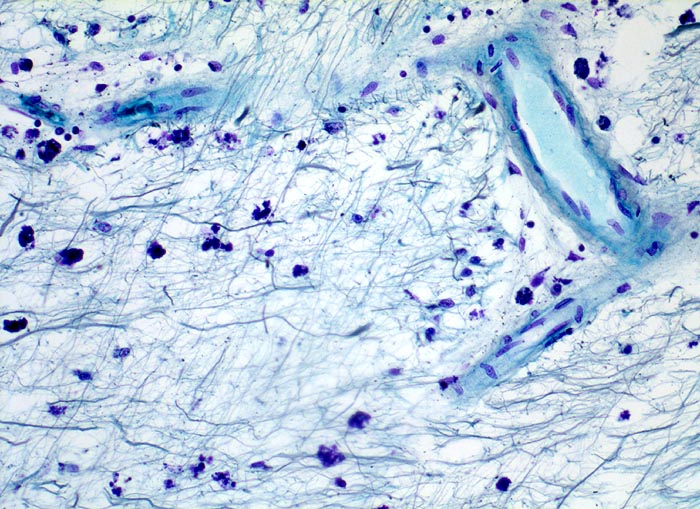

Multiple Sklerose

Entzündung / Reparatur

Hirn temporal

Ausschnitt aus einem älteren Entmarkungsherd. Zwischen den übgriggebliebenen Axonen lassen sich mit Myelinbruchstücken beladene Makrophagen nachweisen. Vereinzelte mononukleäre Entzündungszellen sind vorwiegend perivaskulär lokalisiert. Oligodendrogliazellen sind nicht sicher erkennbar.

Multiple periventrikulär gelagerte Entmarkungsherde im MRI

Histologie

200